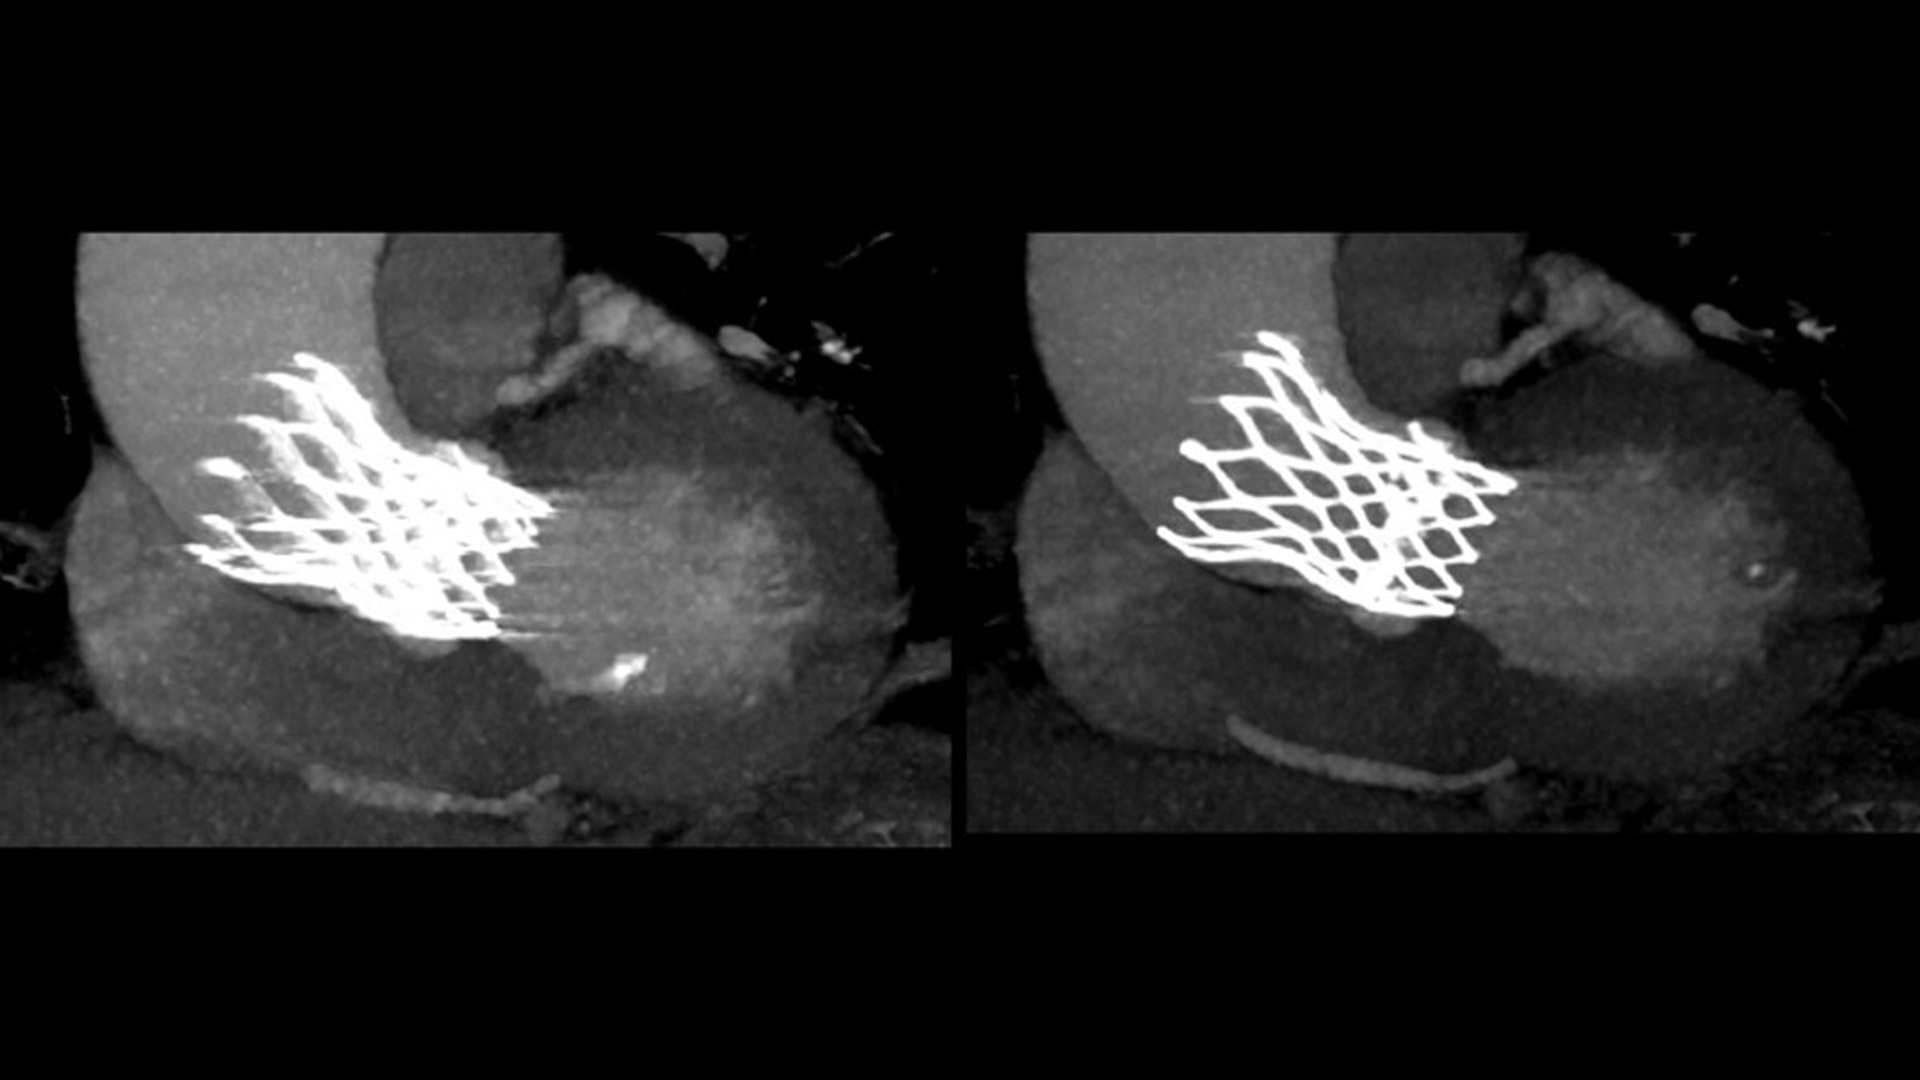

SnapShot Freeze 2

Intelligent and automated whole-heart motion correction for enhanced Cardiac CT imaging.

Temporal resolution

19.5 msec effective temporal resolution at 0.23s/rotation gantry speed2

1. As demonstrated in mechanical and mathematical cardiac phantom testing

2. SnapShot Freeze 2, in conjunction with 0.23 s/rotation gantry speed, provides a reduction in coronary motion artifacts that is equivalent to a 0.039 s/rotation equivalent gantry rotation speed with effective temporal resolution of 19.5 msec. As demonstrated in phantom testing using a commercially available motion phantom and also with a mathematical cardiac phantom with linear motion of variable velocity. The 0.039 s/rotation images are modeled without application of SnapShot Freeze 2. Results may vary in clinical applications.